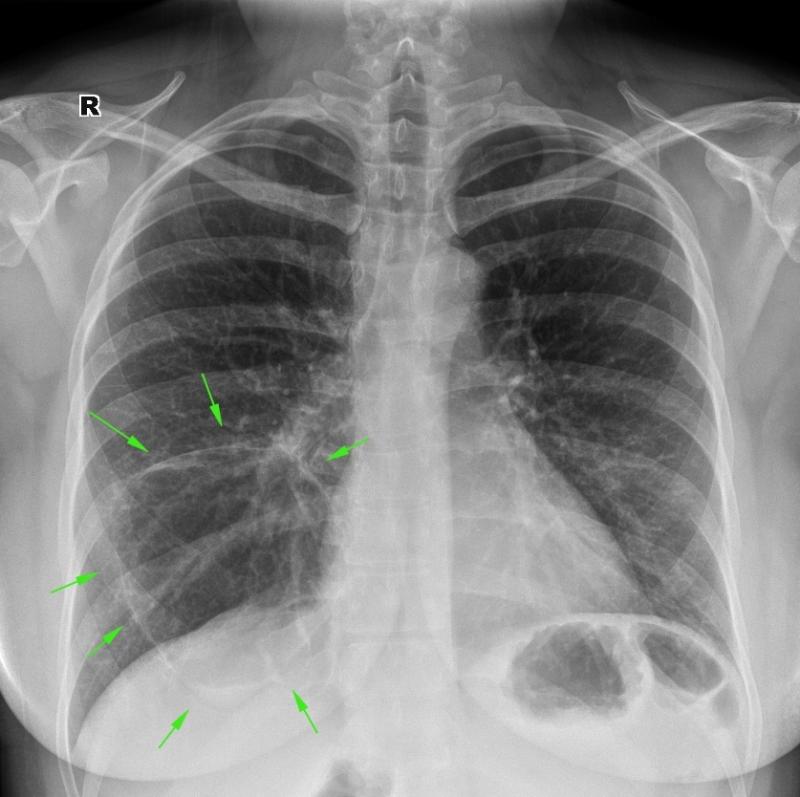

Нормальная рентгенограмма легких: что нужно знать